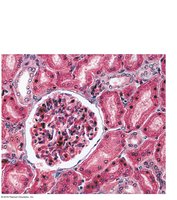

Renal Corpuscle: Includes the glomerulus (fenestrated capillary bed) and Bowman’s capsule (with podocytes forming filtration slits).

Filtration Membrane

The filtration membrane consists of three layers: fenestrated endothelium, basement membrane, and podocyte filtration slits. It allows passage of water, ions, glucose, amino acids, and small proteins, but restricts blood cells and large proteins.

Kidney Disease: Often due to diabetes or hypertension; symptoms include high BP, edema, proteinuria; treated with BP control, diet, dialysis, or transplant.

Acute Glomerulonephritis (AGN): Autoimmune inflammation of glomeruli; symptoms include proteinuria, hematuria, edema; treated with BP control, antibiotics, anti-inflammatories.